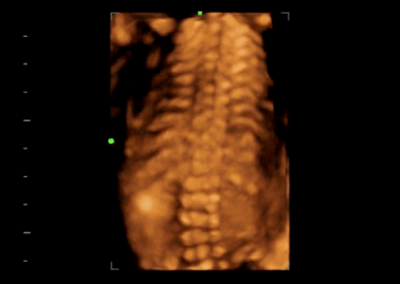

Z60

Sistema de diagnóstico ecográfico.

El sistema Z60 es una buena opción para aquellos que requieren un rendimiento de imagen de alta calidad, una movilidad simple y asequibilidad cuando se trata de imágenes ecográficas avanzadas. Con configuraciones completas y un diseño integrado, el Z60 es el resultado de los esfuerzos continuos y decididos de Mindray para hacer que la atención médica primaria sea más eficiente, eficaz y accesible para todos.